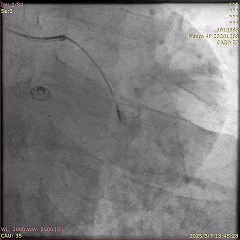

冠脉造影示:冠状动脉弥漫性粥样硬化斑块,左前降支(LAD)次全闭塞,回旋支(LCx)中段存在一处模糊病变,TIMI血流接近正常3级,右冠状动脉为LAD提供侧支循环(Rentrop 3级)。

首次PCI的冠脉造影

基于动态心电图变化情况进行综合分析,确定LAD为罪犯病变,成功植入药物洗脱支架进行治疗,并对第一对角支进行了血管成形术。术后患者胸痛缓解,转入CCU。

首次PCI的冠脉造影(植入支架后)